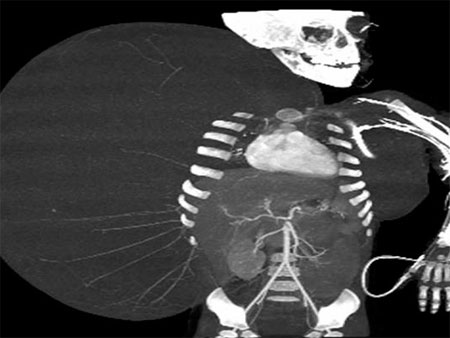

Un equipo de cirujanos del Centro Médico La Raza, del Instituto Mexicano del Seguro Social, logró extirpar un tumor de 15 kilos a un menor de dos años.

El pequeño Jesús Gabriel, originario del estado norteño de Durango, fue sometido a un procedimiento que se extendió por 10 horas, el pasado 14 de junio.

Los médicos tratantes indicaron en una conferencia de prensa que el pequeño nació con una malformación que desembocó en un tumor, este se desarrolló a tal nivel que logró superar su peso corporal. Antes de la intervención, Jesús Gabriel pesaba 27 kilos en total.